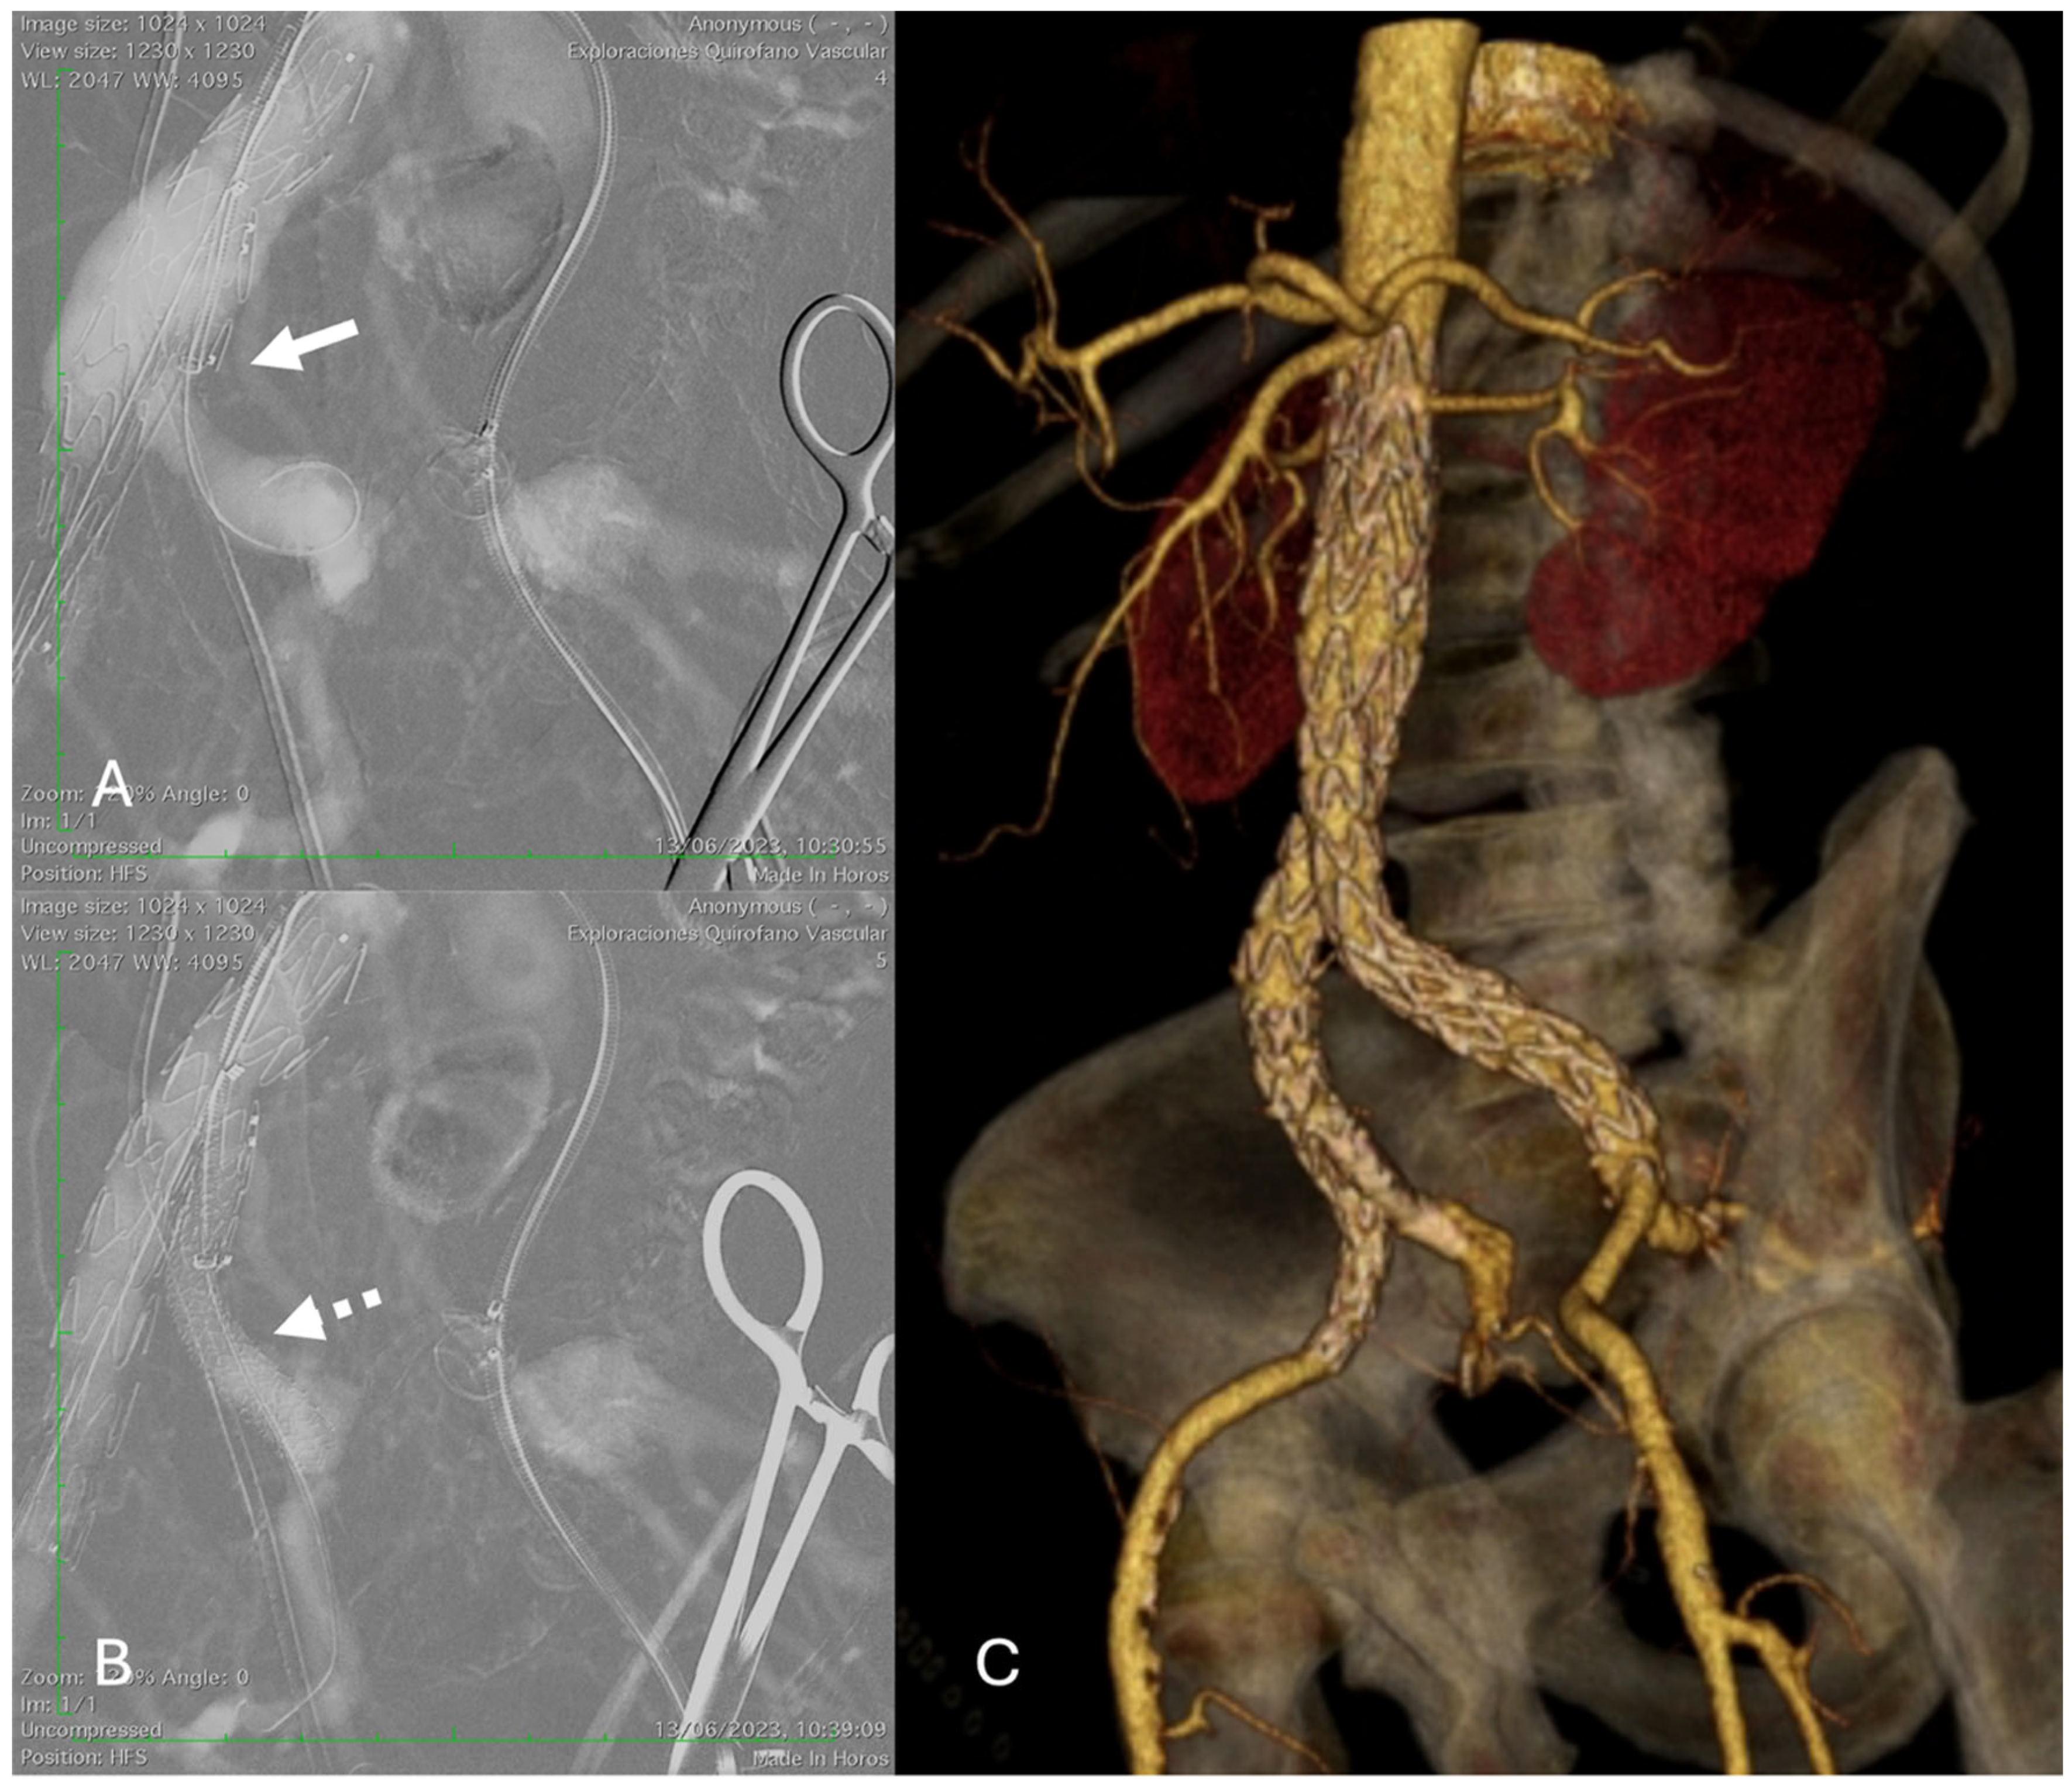

Figure 1. E-tegra (Artivion/Jotec) and E-liac stent-graft system (Artivion/Jotec) implantation in a patient with an infrarenal AAA and right common iliac artery aneurysm. (A) Digital subtraction CO2 angiography shows the main limb of the device deployed with the markers facing the iliac stump (white arrow) and cannulation of the stump and the right internal iliac artery. (B) The bridging stent (E-ventus 9 × 57 mm, Artivion/Jotec) was placed into the right internal iliac artery (dotted white arrow). (C) At 12-month follow-up, 3D reconstruction CT angiography shows successful exclusion of the aneurysms.

Demographics, clinical status, medical history, and procedural aspects were recorded. IBD implantation was performed using the technique previously described by Mylonas et al. [9]. A dual antiplatelet regimen of aspirin (100 mg daily) and clopidogrel (75 mg daily) was initiated after the procedure for at least 4 weeks, followed by lifelong continuation of single-agent antiplatelet therapy (Figure 1).

Final angiographic assessment using digital subtraction angiography (DSA) was performed after each intervention to document the implanted stent site and evaluate downstream vessel patency for evidence of endoleaks or other complications (such as external or internal iliac dissection, thrombosis, or embolism). However, in patients at high risk of complications from iodinated contrast medium, such as those with a history of allergic reaction or impaired renal function (eGFR < 30 mL/min/1.73 m2), CO2-DSA was used.